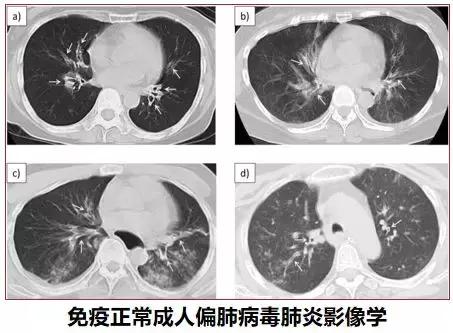

在以前我们对于偏肺病毒的关注度也是相对较少。2018年JID杂志报道了免疫功能正常偏肺病毒感染成人105人,49%患者出现肺炎,肺炎患者呼吸衰竭比例31%,影像学多表现为双侧、中/下肺、散在的、小叶性渗出、气管壁增厚。因此在临床上的重症肺炎的病人,我们现在不能仅仅把眼光局限在细菌感染、真菌感染或者非典型病原体感染,也要把我们的视野扩展到病毒性肺炎。